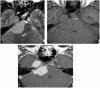

Intracranial trigeminal schwannomas are rare tumors. Patients usually present with symptoms of trigeminal nerve dysfunction, the most common symptom being facial pain. MRI is the imaging modality of choice and is usually diagnostic in the appropriate clinical setting. The thin T2-weighted CISS 3D axial sequence is important for proper assessment of the cisternal segment of the nerve. They are usually hypointense on T1, hyperintense on T2 with avid enhancement post gadolinium. CT scan is supplementary to MRI, particularly for tumors located in the skull base. Imaging plays a role in diagnosis and surgical planning. In this pictorial essay, we retrospectively reviewed imaging findings in nine patients with pathologically proven trigeminal schwannoma. Familiarity with the imaging findings of intracranial trigeminal schwannoma may help to diagnose this entity.